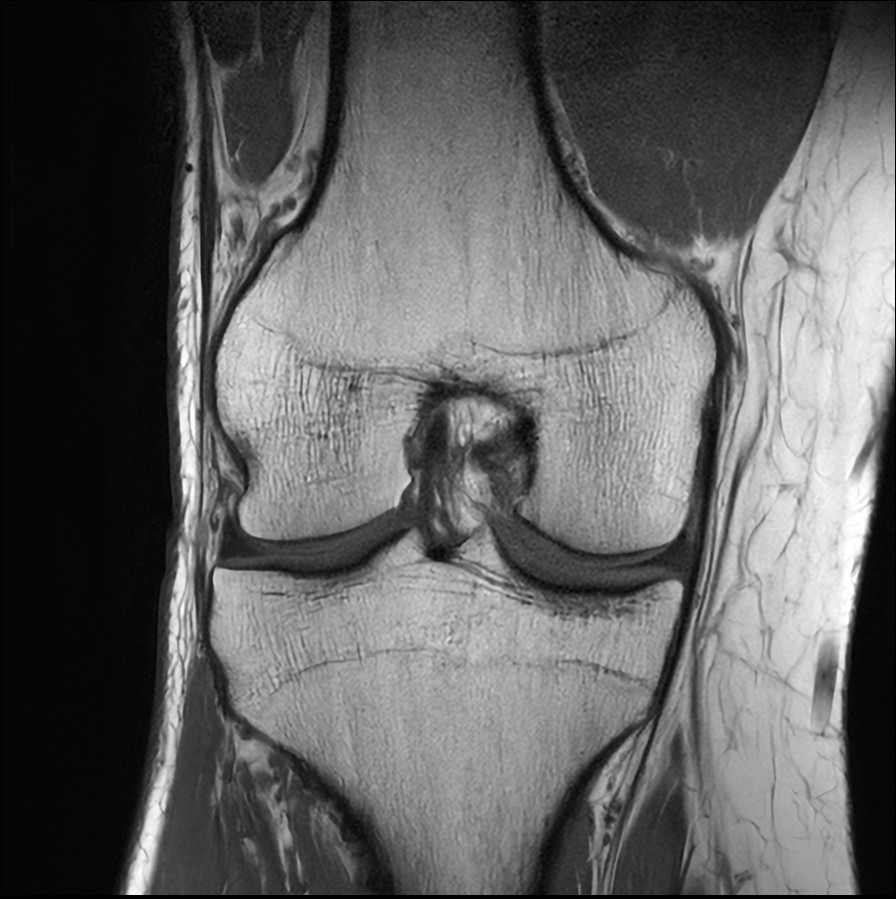

Fast Knee imaging with SmartSpeed Precise

• Clinical Application